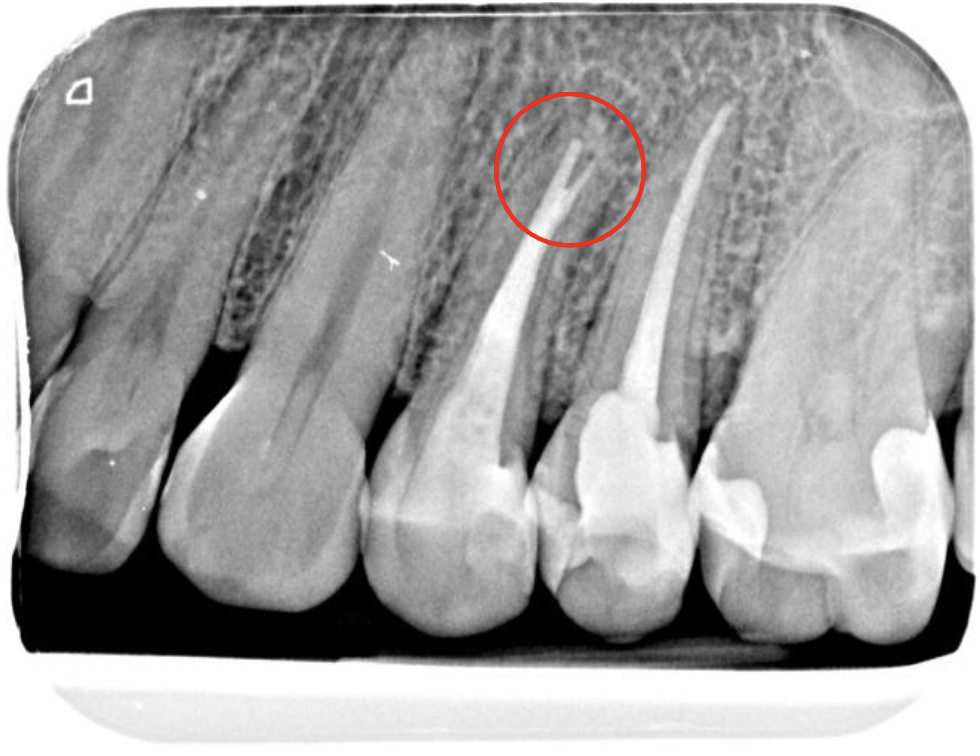

Immediate Post-Op IOPA

Having this information preoperatively made the management of this case far more predictable and underlines why a small field of view high-resolution CBCT scan can be invaluable in the management of most re-treatment cases and arguably most primary cases too. Please follow the link for the most current guidance on the use of CBCT in endodontics (https://onlinelibrary.wiley.com/doi/10.1111/iej.13187). At the first visit, the existing root filling was removed using Reciproc blue R25 and prepped using R40 rotary files and the previously unfilled buccal branch was prepared with the reduced taper (4%) VDW Rotate 1504, 2005 and 2504 files, which is one of my favourite file systems. After lots of irrigation and PUI, the tooth was dressed using calcium hydroxide, and the tooth was well sealed for a month. The aim of this was to try and reduce the swelling and alleviate this lady’s symptoms, which it did really nicely. At the second visit, the tooth was further disinfected and re-obturated using WVC and TotalFill BC sealer Hiflow. It was then returned to the RD for cuspal coverage without delay. I plan to review this case in a year's time, so I will update this case study with new radiographs when I have them.